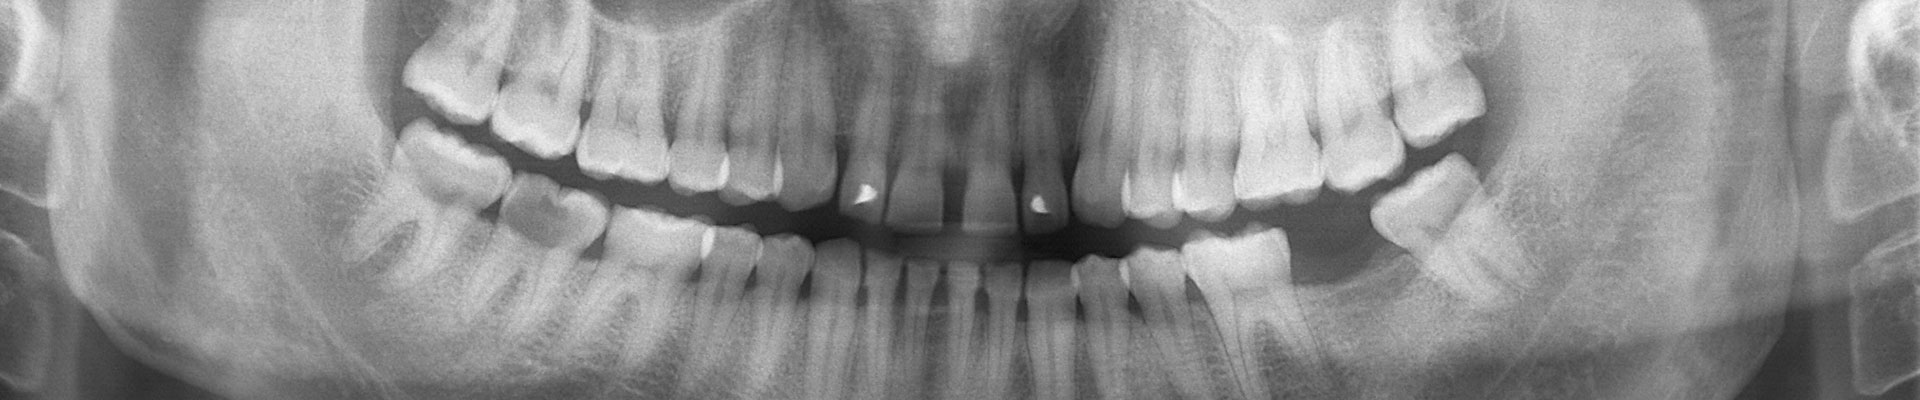

Cuando los dientes no están colocados en una posición correcta, la arcada superior no encaja adecuadamente con la inferior, lo que obliga a desviar la mandíbula para lograr un mejor ajuste entre las dos arcadas, forzando por tanto las articulaciones.

- Malposiciones de los dientes contribuyendo a contactos no adecuados.

- Oclusión no estable.